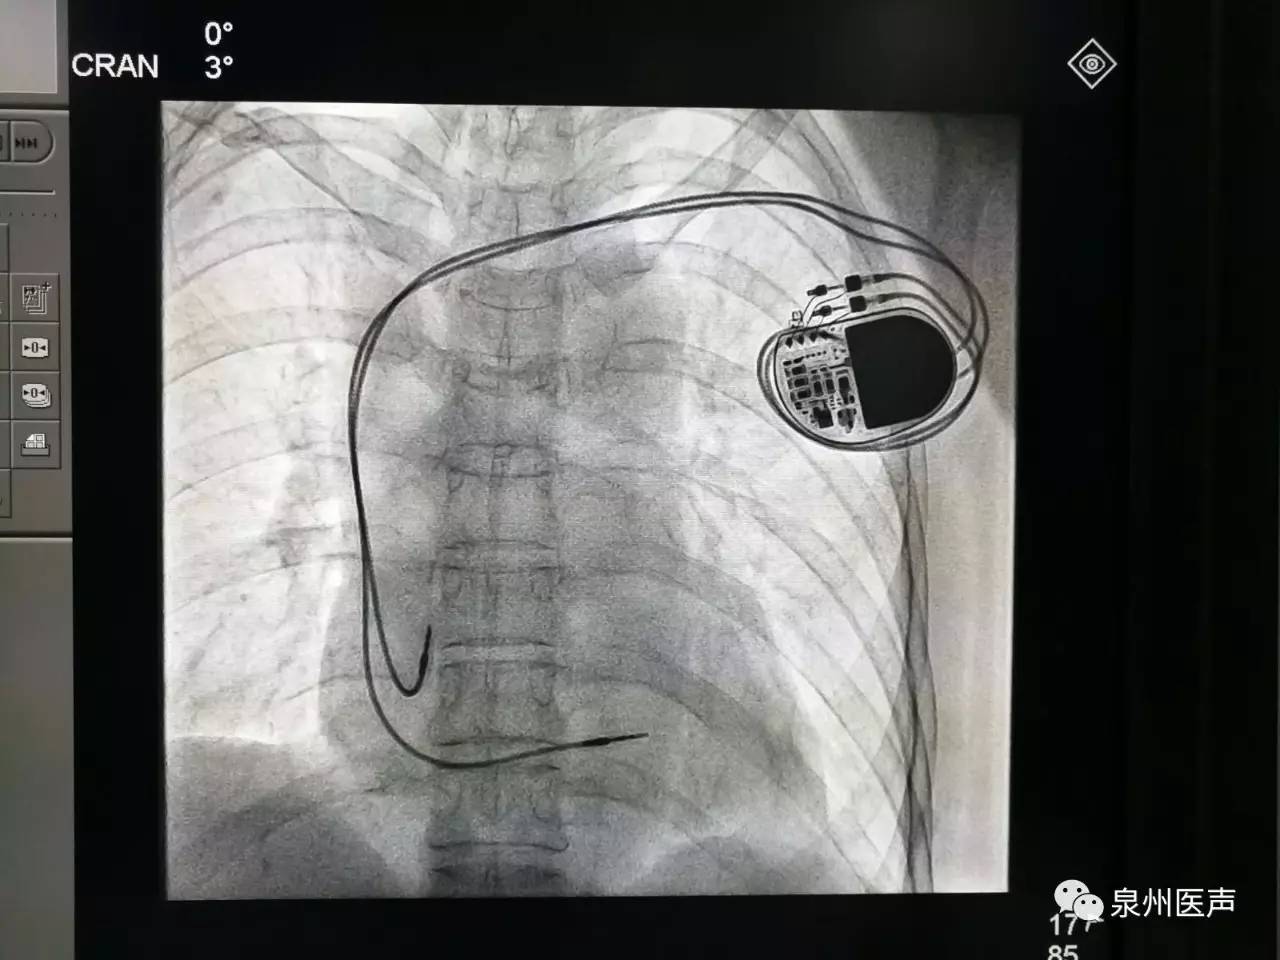

全球唯一!無線雙腔起搏器首次植入

來源:器械之家,未經(jīng)授權(quán)不得以任何形式轉(zhuǎn)載,且24小時后方可轉(zhuǎn)載。2022年2月7日雅培宣布,其在研型Aveir?雙腔無引線起搏器完成了全球首例患者植入,這也是全世界第一個雙腔無線起搏器。Aveir?DR雙腔起搏器提供右心房和心臟右心室的同步、逐次跳起搏,近80%接受起搏器治療的患者需要雙腔選擇,A